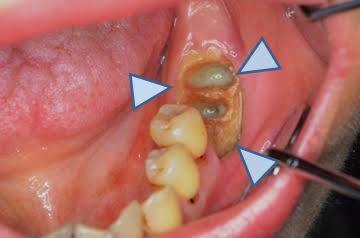

オーラルエステです今日は被せ物(補綴物)の種類を紹介

インレー

クラウン

ブリッジ